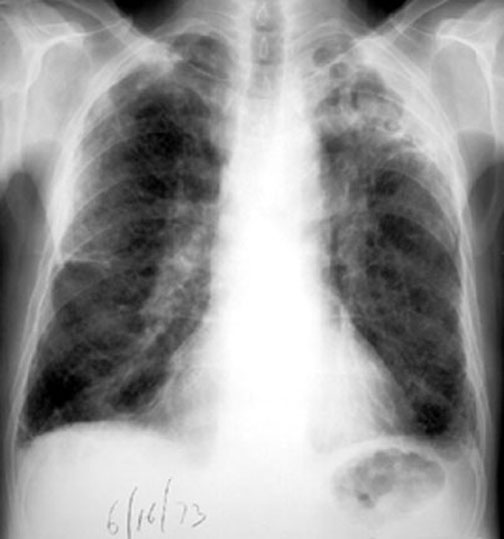

Case 2 Labeled Image What is the differential for multiple cavities?